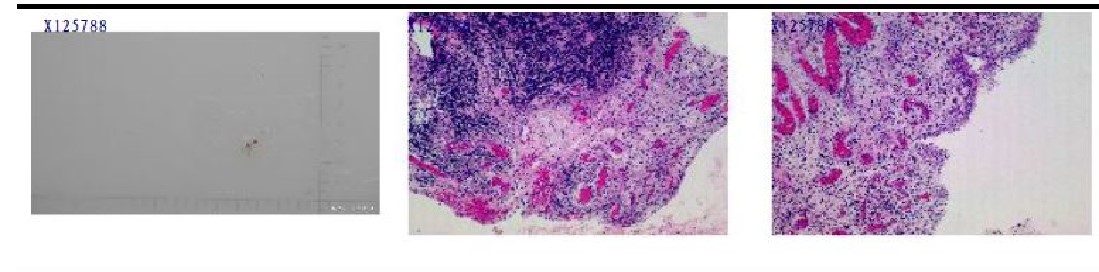

F43, acchieved clinical remmision with normal ESR, CRP and high synovial inflammatory score(7 poionts) in right ankel joint synovium which shows proliferation of synovial cells, interstitial edema, neovascularization, lymphoplasmcytic inflitrates, lymphoid tissue hyperplasia, and infiltration (HE).

F62, failed the treatment of adlimumab and MTX with high synovial inflammatory score(6 points) in left knee joint synovium after 3-months adiministration of adalimumab. Under microscope (HE) , it shows proliferation of synovial cells and fibrous tissue, moderate infliltration of lymphoplasmacytic cells, and inflammatory fibrinous exucdate.